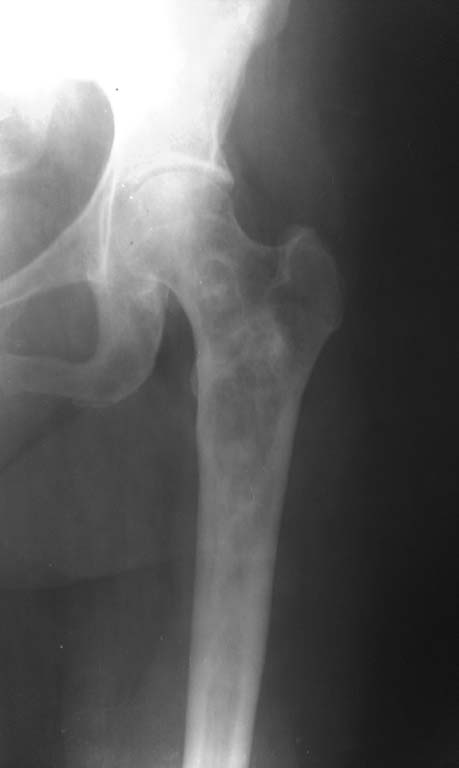

Фиброзная дисплазия проксимального отдела бедренной кости. |

Пациентка 1952 г.р. (61 г.), поступила с жалобами на непостоянные боли в области левого тазобедренного сустава, верхней трети бедра и суставов конечностей. Anamnesis morbi: Со слов пациентки болеет в течении 2,5лет, когда появились боли в бедре и крупных суставах. Об-но: по внутренним органам без особенностей. Пальпаторно отмечается болезненность в проекции верхней – средней трети левой бедренной кости. 04.09.13г 1-м этапом произведена: Операционная биопсия из проксимального отдела левой бедренной кости. Заключение патолого - гистологического исследования: Дегенеративное поражение костной ткани с замещением незрелой фиброзной тканью. В анализах в пределах нормы. Планируем: Резекцию проксимального отдела левой бедренной кости. Тотальное цементное эндопротезирование левого тазобедренного сустава модульным имплантом. Хотелось бы услышать Ваше мнение по тактике и методам оперативного лечения.

Уважаемый доктор Ерсин, что Вас заставляет идти на столь радикальные методы лечения, как резекция части кости, при фиброзно-кистозной дисплазии бедренной кости. Чтобы идти на столь радикальный метод хирургического лечения, нужно иметь весомые доказательства о мальгинизации пораженного участки кости, коих нет пока у Вас. Вы можете однозначно утверждать, что болевой синдром у пациентки связан именно с выявленной фиброзной дисплазией? Я бы лично что бы сделал? Конечно выполнил бы трепанбиопсию, за одно создав дефект стенки кисты, чтобы снизить давление внутри полости выявленной кисты. При отсутствии, по результатам гистологического исследования, злокачественности процесса в кости, я просто наблюдал бы. Потому что, у данной пациентки пока, из представленных снимков, не вижу угрозы перелома. Возможно, после "разгерметизации" кисты, дальнейшая резорбция кости прекратится. Пока рано обрекать пациентку на эндопротез, тем более, на такой, который Вы предлагаете.

Но проблема в данном случае в том, что полость находится месте с высоким стрессом и риском перелома.

Я бы делал кюретаж образования и профилактическую фиксацию цефаломедуллярным стержнем (гамма или что-то подобное).

Следующий вопрос: чам заместить полость: любая кость, и ауто- и (в меньшей степени) алло- в условиях фиброзной дисплазии может резорбироваться. Варианты из литературы: кортикальный аллографт, цемент. Но тут нужно литературу посмотреть еще.